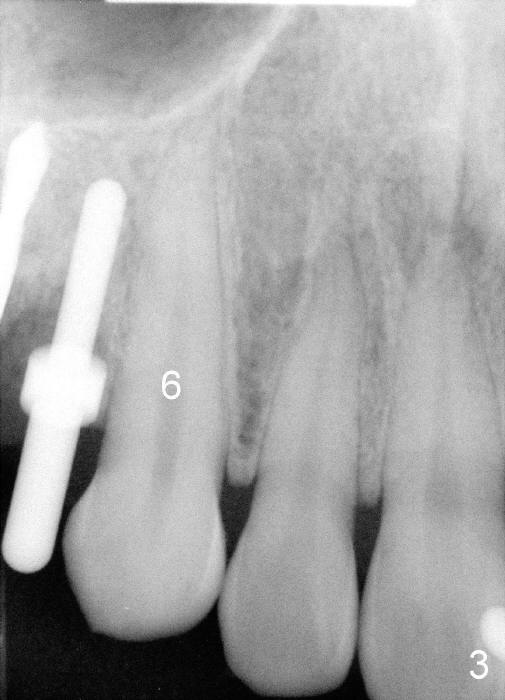

3. PA device, for lower posterior, use endo device; for upper, regular; for upper premolar, anterior if root and bone are long.  Today the patient’s mouth is small.  No.1 sensor was used with anterior PA device later (Fig.4-6)

9. Fig.2,3 show pilot drill and guiding pin at the sites of #4 and 5, respectively.  Thanks to our joined effort, the axis of the implant at the site of #4 was corrected from Fig.4 to 6